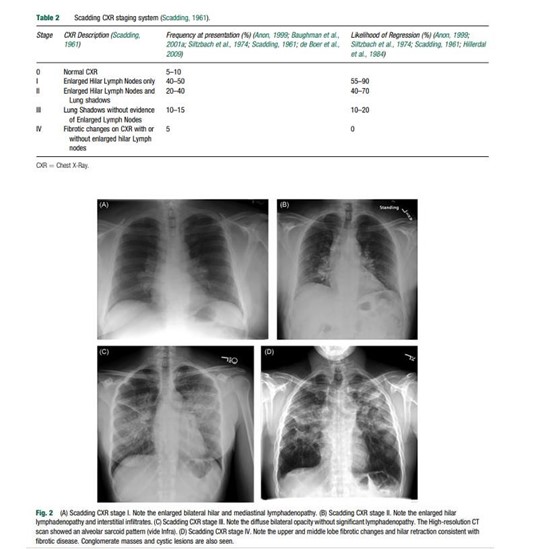

Las radiografías de tórax anormales son comunes en pacientes con sarcoidosis, presentándose en más del 90% de los casos. Se observa linfadenopatía hiliar bilateral en 50%-80% de los pacientes y opacidades pulmonares parenquimatosas en 25%-60% de los casos. Para la estadificación de la enfermedad pulmonar se utiliza el sistema de puntuación radiográfica Scadding, que se basa en la presencia de adenopatías y opacidades pulmonares.

- La enfermedad en estadio I se caracteriza por la presencia de adenopatías hiliares y mediastínicas bilaterales, con una alta probabilidad de remisión radiográfica y sintomática.

- En el estadio II se observan opacidades pulmonares no fibróticas junto con linfadenopatía hiliar y mediastínica, y también hay una alta probabilidad de remisión espontánea.

- En el estadio III se presentan anomalías parenquimatosas no fibróticas sin adenopatías, y la regresión espontánea es menos común.

- El estadio IV se caracteriza por cambios fibróticos en la radiografía de tórax, con menor probabilidad de regresión espontánea.

La sarcoidosis es una enfermedad multisistémica que afecta principalmente a los pulmones en más del 90% de los casos. Desde el punto de vista del diagnóstico por imágenes, los pacientes son clasificados en cuatro estadios radiológicos según la afectación pulmonar, basada en la clasificación de Scadding.19

- Estadio I: afectación de los ganglios linfáticos hiliares y mediastínicos sin compromiso pulmonar evidente.

- Estadio II: afectación ganglionar junto con opacidades pulmonares.

- Estadio III: afectación pulmonar sin compromiso ganglionar.

- Estadio IV: fibrosis pulmonar avanzada.